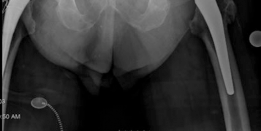

For anyone wondering about Acetabular Revision: Solving Challenges Post Two-Stage Arthroplasty, A **title acetabular revision** is a complex procedure addressing issues like septic loosening, dislocation, and significant osteolysis in total hip arthroplasty. For a 71-year-old male with a dislocated left THA due to infection and periacetabular bone loss, treatment involved a two-stage exchange followed by revision with a press-fit hemispherical cup and screw fixation.